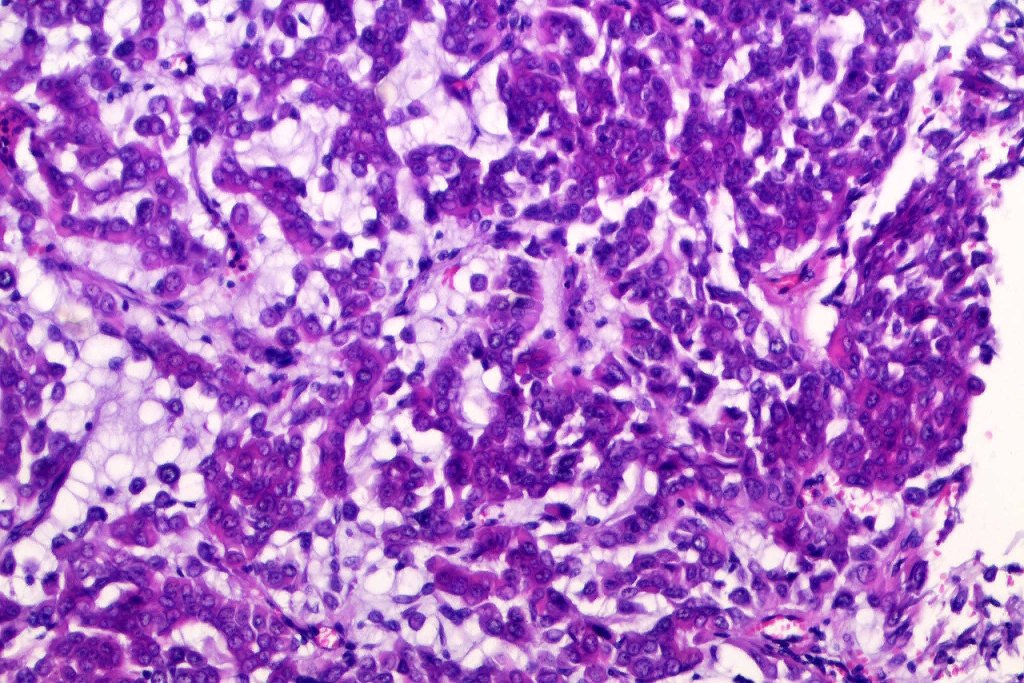

•Mixed epithelial component including nests & cords of epithelium with abundant, eosinophilic cytoplasm & small vesicular nuclei

•Clear cell change

•Glandular differentiation sometimes showing apocrine differentiation

•Myoepithelial layer in glandular foci

•Cribriform/retiform appearance occasionally evident